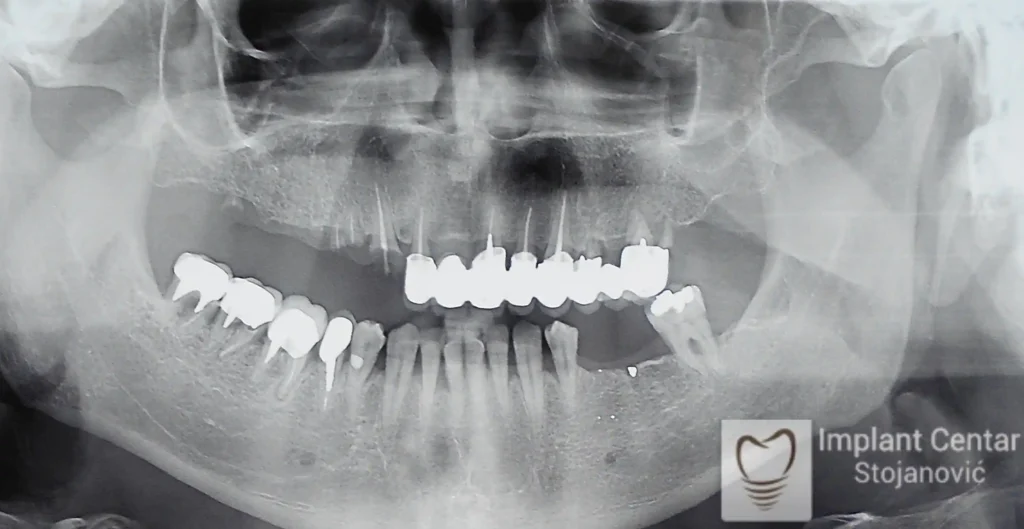

Na slici 1. slici 2. vidi se početno stanje — pacijent je imao prirodne zube, ali samo izradom novih mostova nije bilo moguće postići normalan odnos gornjih i donjih zuba (eugnatan zagrižaj).

Zbog toga je plan terapije uključivao vađenje svih preostalih zuba i ugradnju implantata u gornjoj i donjoj vilici. U gornjoj vilici postavljena su i dva tuberopterigoidna implantata, kao zamena za sinus lift proceduru, što se može videti na ortopan snimku nurađenom odmah nakon ugradnje (slika 3).